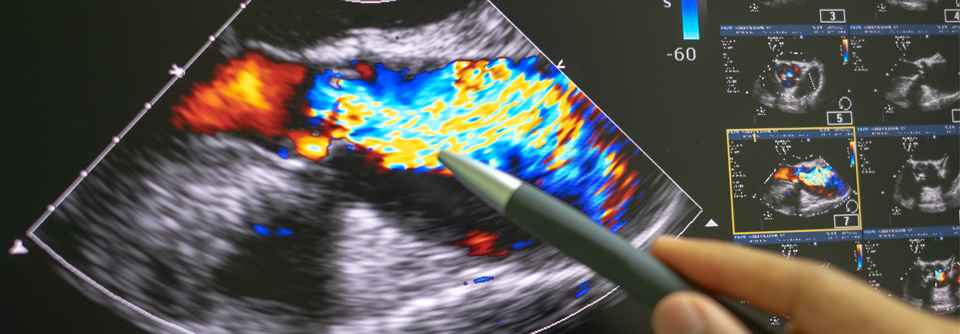

Endokarditis mit dem Messer kurieren

Wann eine Klappen-OP erforderlich wird und welche Möglichkeiten es gibt

Mit der antibiotischen Therapie allein lassen sich nicht immer alle Probleme, die eine infektiöse Endokarditis mit sich bringt, aus der Welt schaffen.…

Kardiologie , Chirurgie , Innere Medizin

Kalk in der Aortenklappe

Das optimale Vorgehen bei Stenosen

Unbehandelt geht die schwere kalzifizierte Aortenstenose mit einer hohen Ein-Jahres-Mortalität einher. Ein rechtzeitiger Klappenaustausch kann die…

Kardiologie , Chirurgie